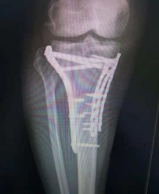

3.胫骨平台骨折